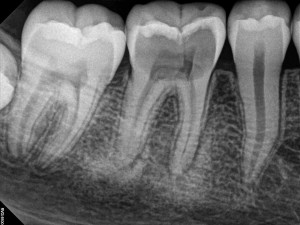

after the root canal has been completed on the tooth.